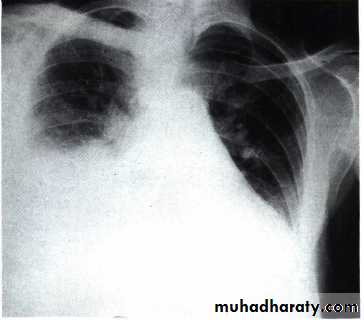

Radiology

Chest X-RayUltrasound (US) is able to demonstrate small effusions.

Chest X ray: The pleural fluid accumulates in the most dependent part of the thoracic cavity

The normally sharp posterior costophrenic angle is obliterated.

Upper surface is meniscus-shaped (meniscus sign).

Around 200 mL of fluid is required in order for it to be detectable

on a PA chest X-ray

The amount of pleural effusion may be small, large or massive.